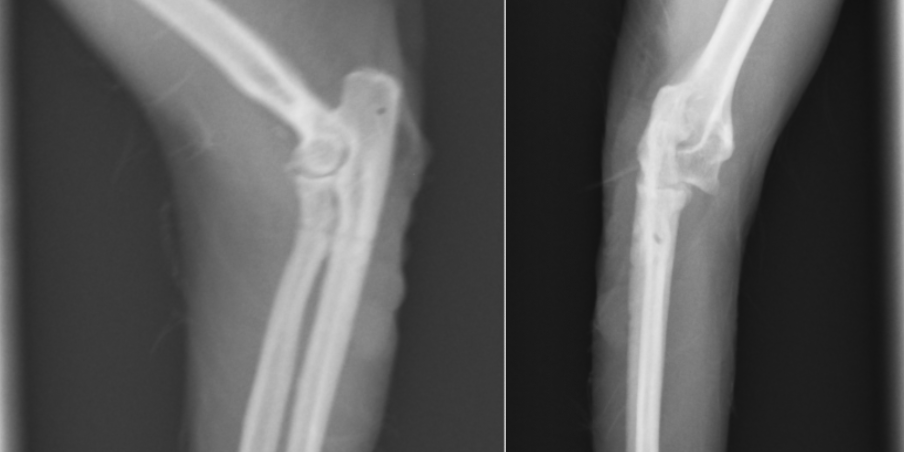

これは正常な方の前肢です。

患肢を正面から見たX線画像です。オレンジの橈骨と緑の尺骨が離れており、脱臼しているのが分かります。

正面像です。こちらでみても橈骨と尺骨があっているのが分かります。